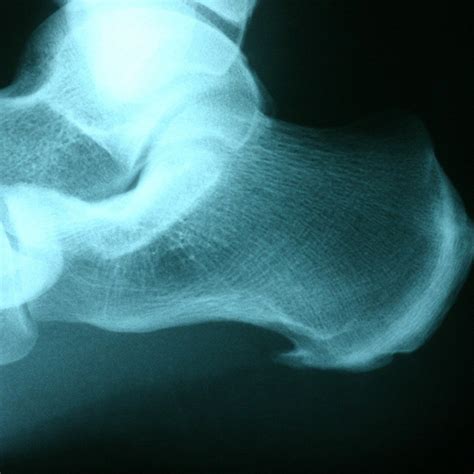

A heel spur, technically known as a calcaneal spur, is a bony protrusion that develops on the underside of the heel bone. Over time, calcium deposits build up on the heel, resulting in this outgrowth. These spurs are often associated with plantar fasciitis, a common condition that involves inflammation of the tissue running along the bottom of the foot.

It is important to note that many individuals possess heel spurs without ever experiencing any pain. The pain often stems not from the spur itself, but from the associated inflammation of the soft tissues surrounding the heel bone. This is precisely why a Heel Spur X Ray is ordered—to visualize the bone structure and help the physician determine whether the spur is the primary culprit or if other factors are contributing to your symptoms.

• Visualization: It provides a clear, high-contrast view of the heel bone, allowing the doctor to see the exact size and location of any bony growth.

Once the radiologist examines your Heel Spur X Ray, they will generate a report for your doctor. It is common for the report to confirm the presence of a "calcaneal spur." However, as mentioned previously, this does not automatically mean the spur is causing your pain. Your physician will correlate these findings with your physical symptoms. For instance, if your pain is worst in the morning or after long periods of sitting, the clinical focus will likely remain on treating the underlying plantar fasciitis, even if a spur is visible.